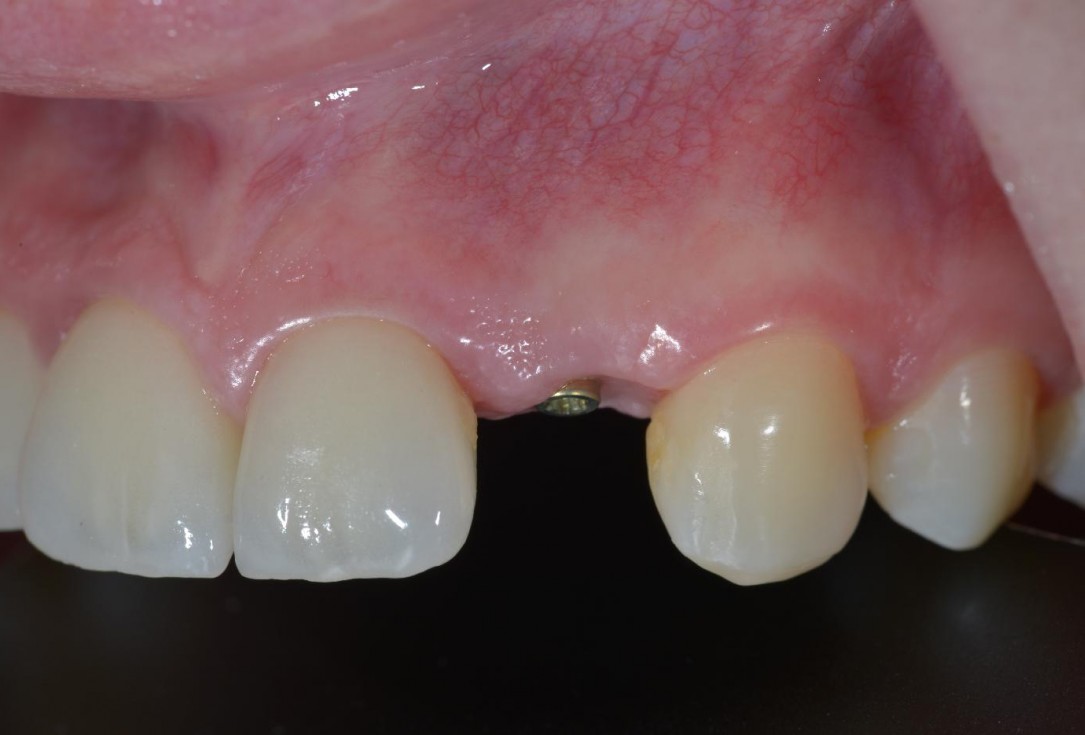

9/12 - Soft tissue at 12 weeks, lateral viewSoft tissue thickening at immediate implant placement and GBR with mucoderm® and maxgraft® - Dr. A. Puisys